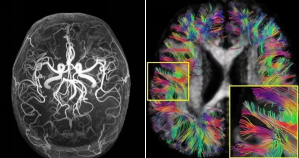

5.0T超高场高分辨成像效果(左:血管成像;右:脑神经纤维束成像)

国际首创5.0T超高场全身磁共振